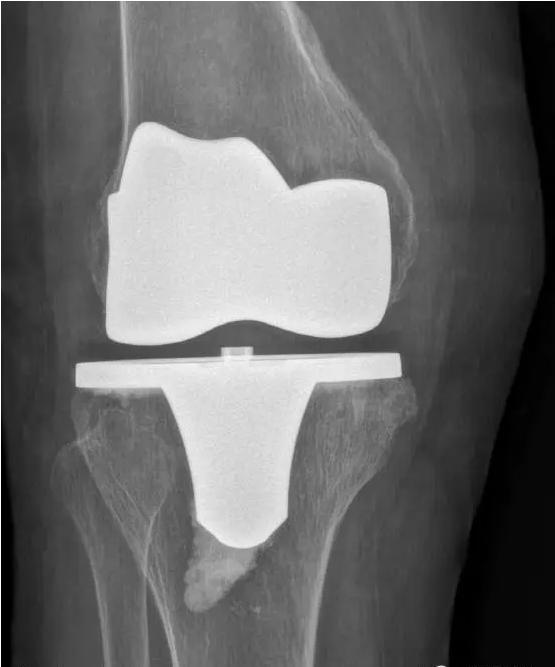

对于晚期(重度)骨关节炎,保守治疗无效时,要积极考虑手术治疗。目前效果最佳的手术方式即为关节置换手术,其他手术方式如关节融合手术等效果较关节置换术相差较大,已不在临床广泛使用。关节置换手术的目的是缓解患者疼痛,矫正关节畸形,恢复关节功能,恢复正常生活。对于老年人来说,积极的手术治疗可以有效恢复其日常生活,避免因疼痛及活动障碍导致患者扶拐或坐轮椅,有效减少因缺乏运动导致的心肺功能障碍及精神问题发生。经过几十年的发展,目前关节置换技术已十分成熟,临床上目前采用的微创技术,手术创伤小,术中出血非常少,术后第二天患者即可下地行走,三月之后即可恢复正常生活及功能。至于人工假体使用寿命,目前进口关节多为20-30年,能满足60-70岁患者的需求。需要关注的是,在行关节置换手术之后,患者仍需要进行积极的康复治疗,包括关节活动度及周围肌力的锻炼等,这样才能达到最佳的手术效果。

术后图如下: